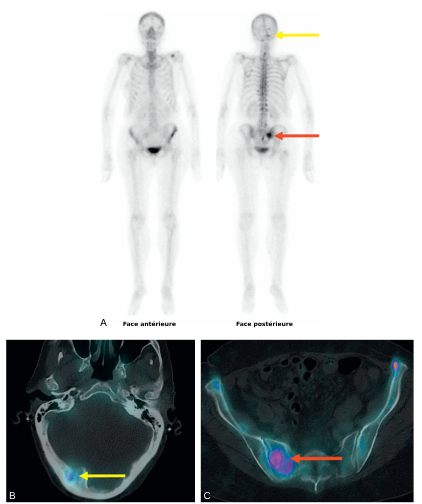

La TDM thoraco-abdomino-pelvienne est indiquée dans le bilan initial des cancers à risque élevé de métastases en association avec une scintigraphie osseuse (figure 34.1), ou une TEP-TDM au 18FNa si la technique est disponible.

Fig. 34.1 Bilan d’extension par scintigraphie osseuse « corps entier » (A) et couplée à la TDM (B, C) d’un cancer du sein, mettant en évidence des lésions osseuses mixtes, à prédominance ostéolytique, hyperfixantes, notamment de la base du crâne (flèches jaunes) et de l’aileron sacré droit (flèches rouge).

Source : CERF, CNEBMN, 2022.